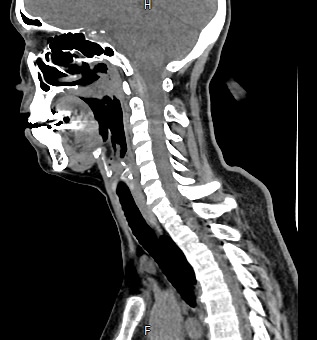

В ходе исследования хорошо визуализируются хрящевой каркас гортани, голосовые складки, голосовая щель, близлежащие органы и окружающие ткани. Помимо гортани на изображениях можно оценить состояние трахеи, носоглотки, щитовидной железы, шейных позвонков, сосудов, нервов и лимфоузлов.

Кроме того, полученные снимки дают возможность воссоздать трехмерную модель анатомической области, включая гортань и близлежащие органы, оценить точную локализацию патологических структур, их размеры и степень воздействия на окружающие ткани.